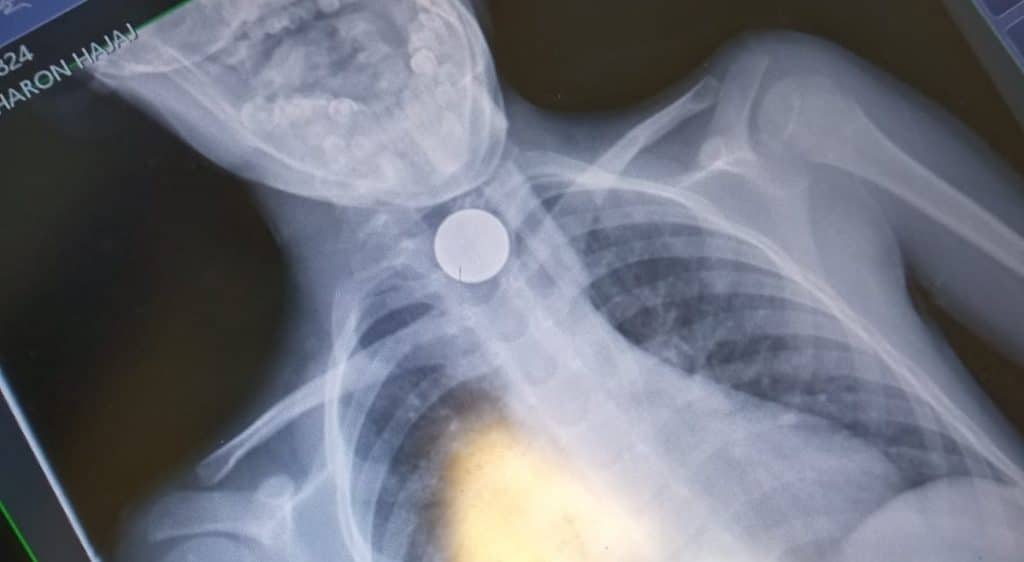

אפי פלדמן ראש סניף איחוד הצלה בבני ברק סיפר: "כשהגעתי למקום נמסר לנו כי הילד נחנק ממטבע של 10 אגורות שנתקע לו בקנה הנשימה. פיניתי אותו באמבולנס איחוד הצלה למרכז הרפואי מעייני הישועה תוך כדי שייצבנו את מצבו".